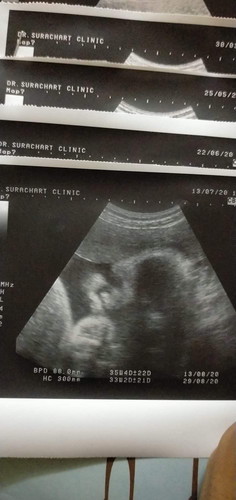

32w น้องน้ำหนักเยอะไปไหมคะ

หมอบอกน้องตัวโตมาก หัวโตมากให้เลิกบำรุงได้แล้วนะคะคุณแม่เด่วจะออกยาก น้องหนัก2560กรัมแล้ว 32w เอง มีบ้านไหนอายุครรภ์เท่ากัน น้องน้ำหนักเท่าไหร่แล้วคะ

ซาวด์ตอน32วีค 2228ค่ะ